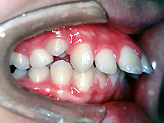

叢生(乱ぐい)

■治療前

上顎前突

下顎前突